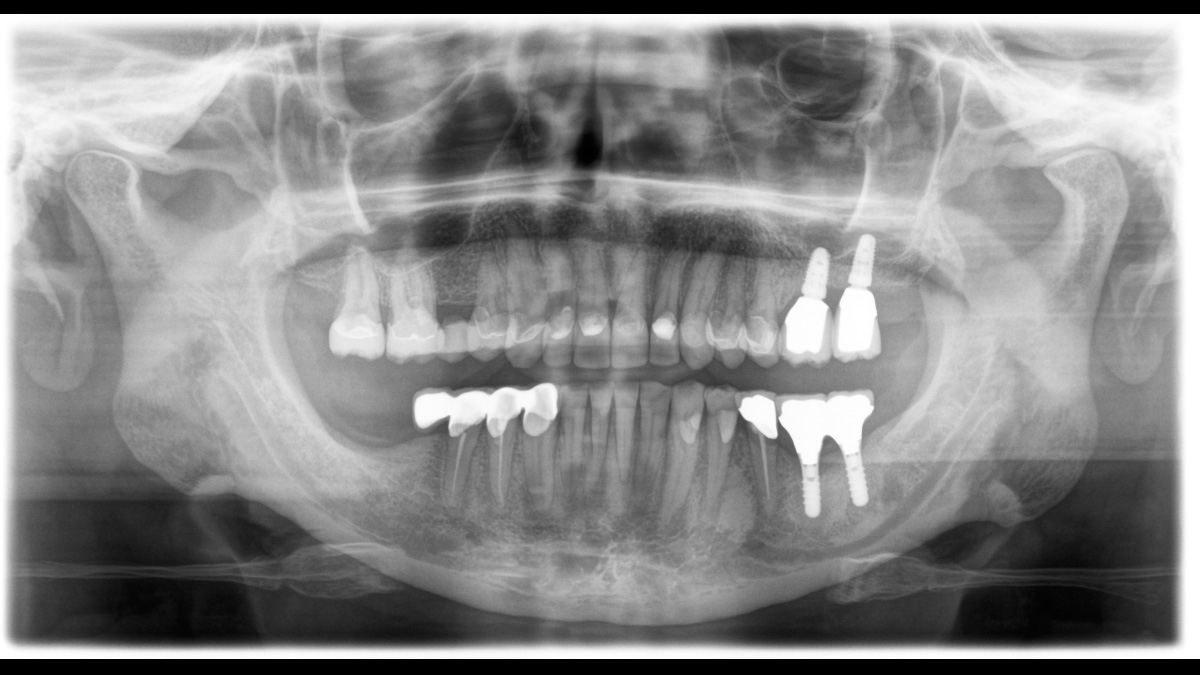

El equipo de radiología 2D/3D de alta calidad con una amplia gama de servicios para cada clínica. Ya sea como un dispositivo puramente 2D o como un módulo 3D, el Orthophos S es un socio confiable y está optimizado para las tareas diarias. Su sensor CsI Plus con función de autofoco garantiza imágenes claras, incluso en casos anatómicamente difíciles. El posicionamiento automático del paciente junto con el bloque de mordida oclusal patentado permite un posicionamiento del paciente fácil y que ahorra tiempo. Para su uso en ortodoncia, la Orthophos S también está disponible con un brazo cefalométrico opcional. Y como para Dentsply Sirona es importante estar preparado para el futuro, el brazo cefalométrico se puede reacondicionar en cualquier momento.

Para la mayoría de las clínicas, se utiliza un equipo de radiología con dos objetivos principales en mente: capturar la mejor imagen posible para respaldar un diagnóstico preciso y exacto, y garantizar que el paciente se sienta cómodo durante el proceso. El Orthophos S ofrece soluciones únicas y patentadas para apoyar ambos objetivos con: